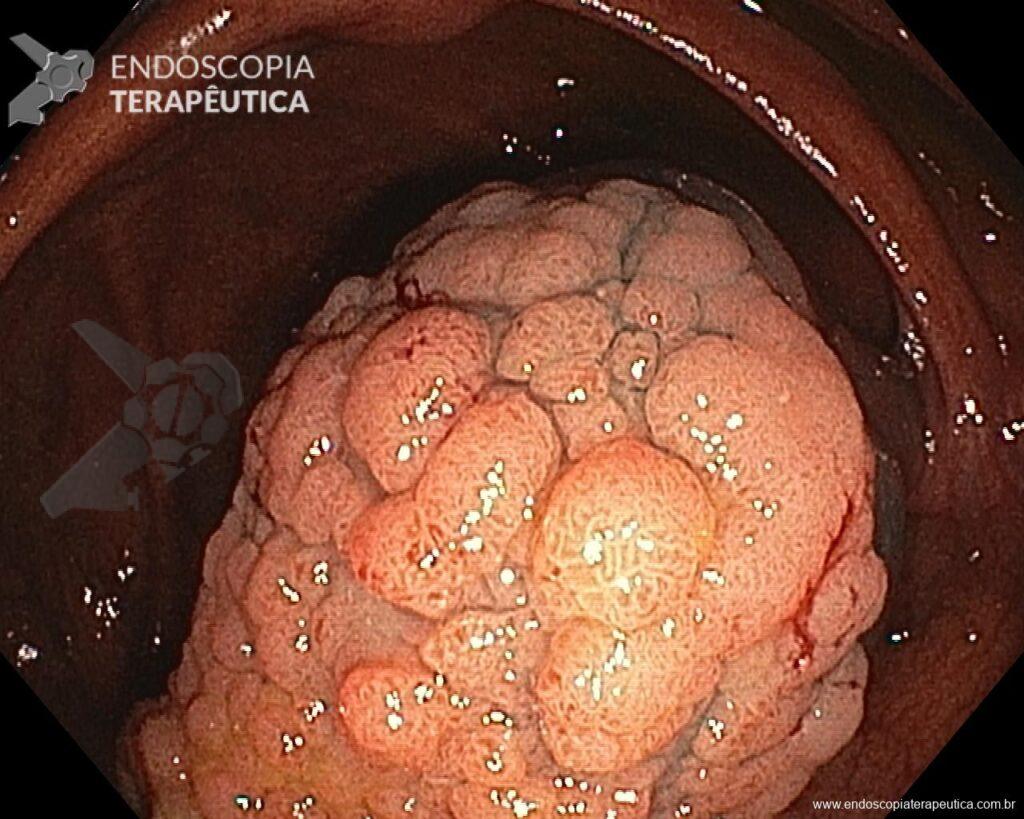

Hombre, 60 años, previamente sano, sin comorbilidades ni historial familiar relevante para neoplasias del tracto gastrointestinal, fue sometido a la primera colonoscopia para fines de rastreamiento/prevención del cáncer colorrectal obteniendo el siguiente hallazgo:

– Lesión plano-elevada de crecimiento lateral (LST), del tipo granular homogénea (LST-G-H), con superficie y vasculatura regulares a la cromoscopia virtual con NBI, midiendo cerca de 4cm, localizada en el ciego (París 0-IIa / JNET 2A).